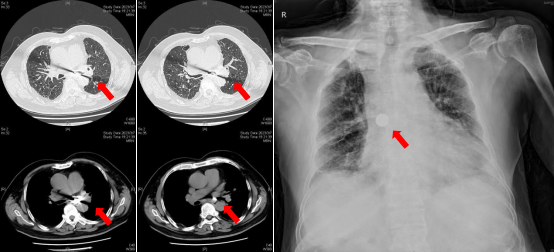

入院胸部CT示左主支气管内硬币大小异物一枚(红色箭头所示)入院第2天复查床旁胸片提示硬币样异物自行转移至右主支气管内(红色箭头所示)。

呼吸与危重症医学科牟向东主任带领的医疗团队立即收患者入院并安排电子支气管镜检查,经口行支气管镜,镜下可见右主支气管内一硬币大小异物嵌顿管口,镜下使用专门的异物钳,快速而稳定地取出异物,时间不到1分钟,张大爷气短、咳嗽症状迅速缓解。